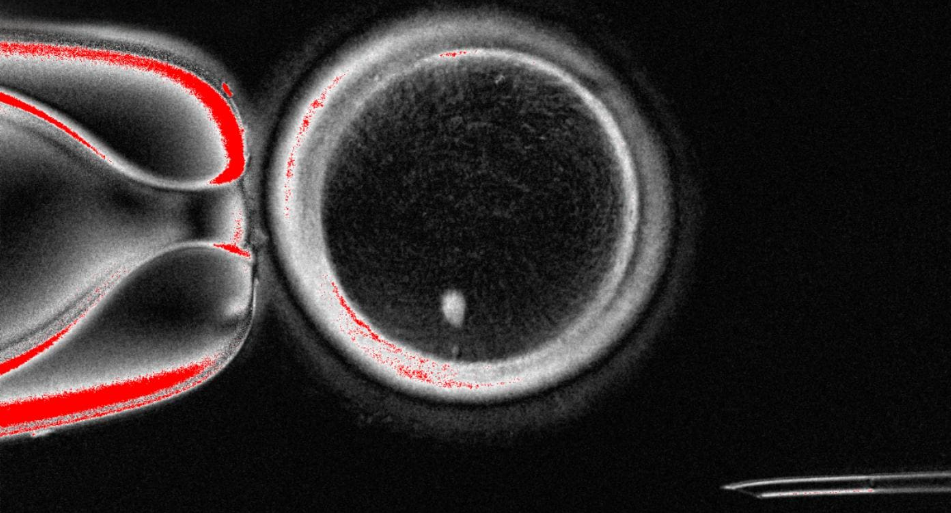

皮肤细胞有望培育受精卵,为不孕提供新希望

科普

囊胚